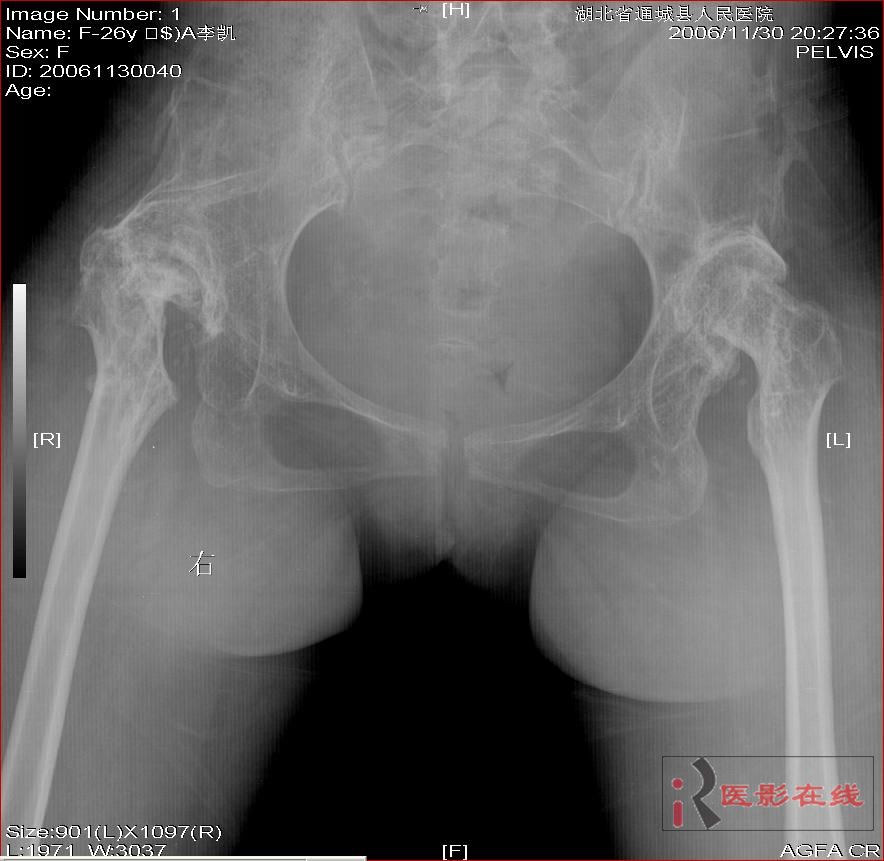

先天性双髋关节脱位自体骨关节再造

女 28岁 先天性髋关节脱位术后复查片(手术日期是2000年,数字化以前平片资料患者外带),现无其它不适,走路仍需双拐

2006年11月30日

1.双髋关节先天性脱位术后改变;2.双髋关节退行性变;3.骨质疏松(骨盆明显)。

双侧髋关节仍为脱位表现,假关节形成,部分已经强直,右股骨头碎裂,股骨干近端增粗。

结合手术史考虑:原地臼盖成形术后,髋关节退变,股骨头无菌性坏死,右股骨近端生长紊乱,骨质疏松。